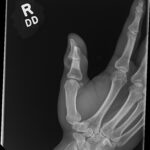

Open fractures represent high acuity injuries requiring rapid evaluation and management for optimal outcomes. In this report, we discuss a patient presenting with an open fracture of the proximal phalanx of the right thumb with interphalangeal (IP) joint dislocation. The patient reported that the injury occurred in the setting of trauma from catching a cricket ball, experiencing immediate severe pain and bleeding. Key interventions in the emergency department included rapid x-ray evaluation of the injury, administration of cefazolin and tetanus vaccine, pain control, covering the exposed bone in moist gauze, and involvement of the hand surgery team for bedside irrigation and reduction. He underwent open reduction and internal fixation of the fracture the next day. He was followed in the hand clinic and was doing well at the 12-week appointment. In summary, we report on an open fracture and dislocation of the proximal phalanx of the thumb secondary to a traumatic cricket injury. Early mobilization of the surgical team and adjunctive prophylaxis with cefazolin and updated tetanus were key measures in the emergency department for achieving optimal outcomes.